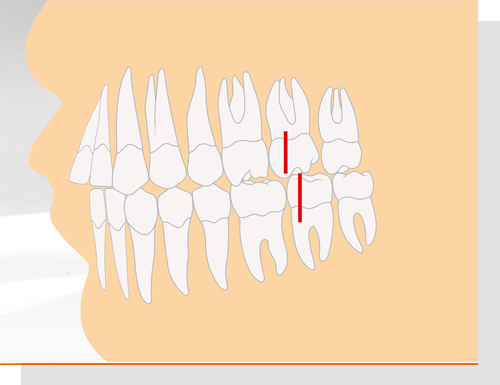

Angle-Klasse II/1

Die oberen Schneidezähne stehen nicht gerade, sondern sind nach außen gekippt. Dadurch kann unter anderem das Abbeißen erschwert sein. Die Fehlstellung beeinträchtigt ebenfalls das Gesichtsprofil. Die vorstehenden Zähne wirken oft zu groß ("Hasenzähne").

Angle-Klasse II/1

Die oberen Schneidezähne stehen nicht gerade, sondern sind nach außen gekippt. Dadurch kann unter anderem das Abbeißen erschwert sein. Die Fehlstellung beeinträchtigt ebenfalls das Gesichtsprofil. Die vorstehenden Zähne wirken oft zu groß ("Hasenzähne").